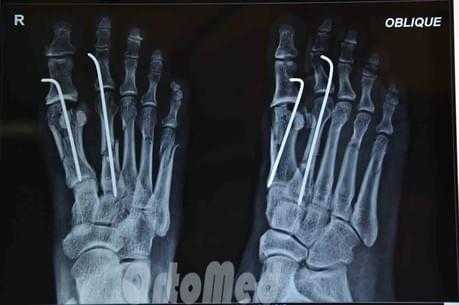

СНИМКИ СТОПЫ В КОСЫХ ПРОЕКЦИЯХ

Информативность .снимков. На снимках видны кости предплюсны: таранная, ладьевидная, кубовидная и клиновидные, суставные щели между ними. Раздельно отображаются все кости плюсны и фаланг, видны их переднебоковые и зад небоковые поверхности. Прослеживаются рентгеновские суставные щели плюснефаланговых и межфаланговых суставов (рис. 449).

В этом случае снимки стоп в косых проекциях по сравнению с другими снимками являются наиболее информативными для выявления переломов плюсневых костей и фаланг (рис. 450, а, б).